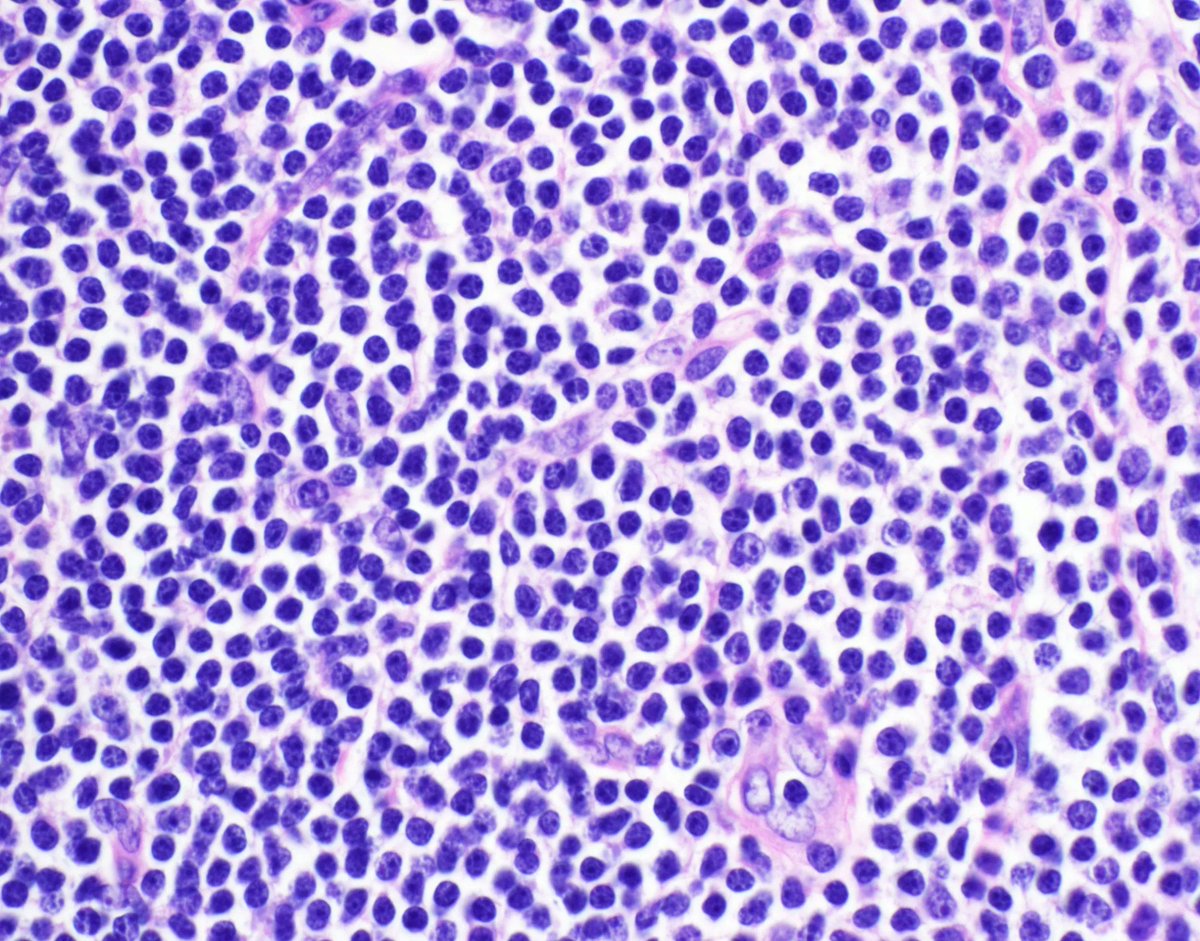

Can you make diagnosis from one pic, or is it #TooCloseToDiagnose? Digital slide: https://t.co/7itVghMPzB. Answer ✅ https://t.co/gcZ4O7uR9m More info: https://t.co/ZAiy3mdO63.

#pathology #pathologists #pathTwitter #dermpath #dermatology #dermatologia #dermtwitter